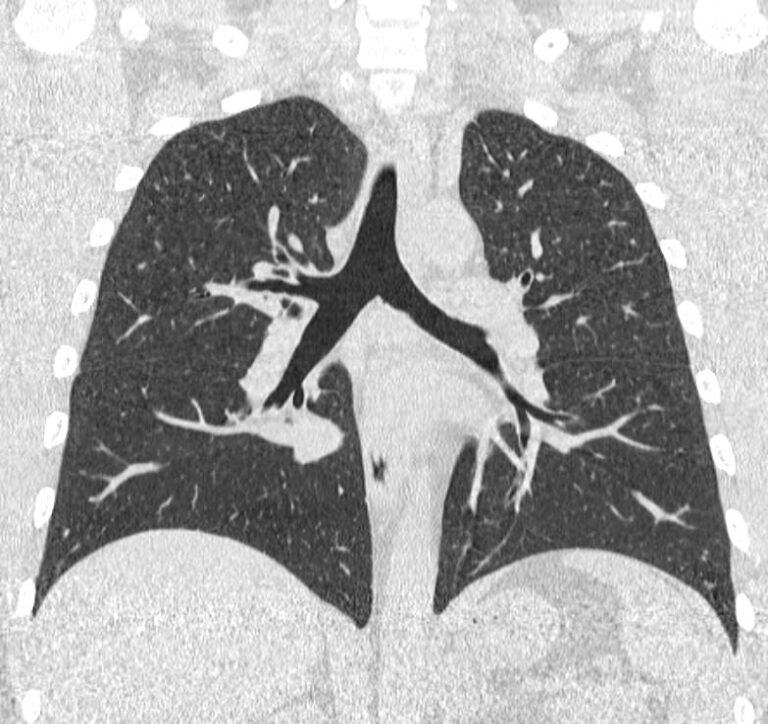

Компьютерная томография бронхов представляет собой виртуальную бронхоскопию, которая позволяет получить точную и достоверную информацию о состоянии трахеи, бронхов, а также оценить структуру легочной ткани, кровеносных сосудов, органов средостения. При обычной бронхоскопии эндоскопический зонд вводится внутрь через дыхательные пути и производится осмотр слизистой трахеи и бронхов, поэтому процедура относится к инвазивным и часто проводится под наркозом.

На основе данных, полученных при сканировании, аппарат создает наглядную 3D модель бронхиального дерева с высочайшей точностью и достоверностью, которая позволяет просматривать интересующие анатомические структуры в разных плоскостях. Метод обладает высокой точностью и дает возможность исследовать мелкие бронхи и бронхиолы, которые из-за узкого просвета бывает невозможно осмотреть при помощи эндоскопической бронхоскопии (возможности метода ограничены размером зонда).